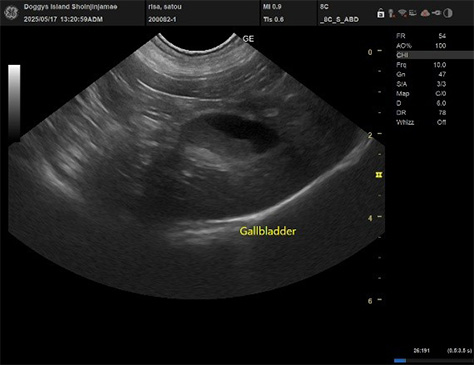

胆泥形成

犬、6歳9か月無症状

- 症状

- 健康診断Cコース

- 来院経緯

- 近所のため

- 診察内容

- 行った処置等

- 診断結果を示しながら飼い主様と相談し治療方針を決定